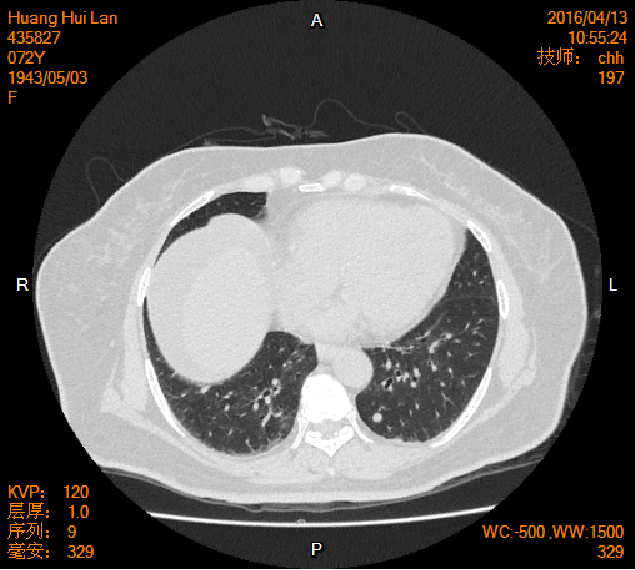

2016-04-13胸腹盆CT

左侧附件区肿块,代谢活跃,考虑卵巢囊腺癌;直肠壁增厚,代谢活跃,考虑直肠癌并周围淋巴结转移可能性大,建议肠镜检查;双肺多发结节,考虑转移瘤;腹腔积液